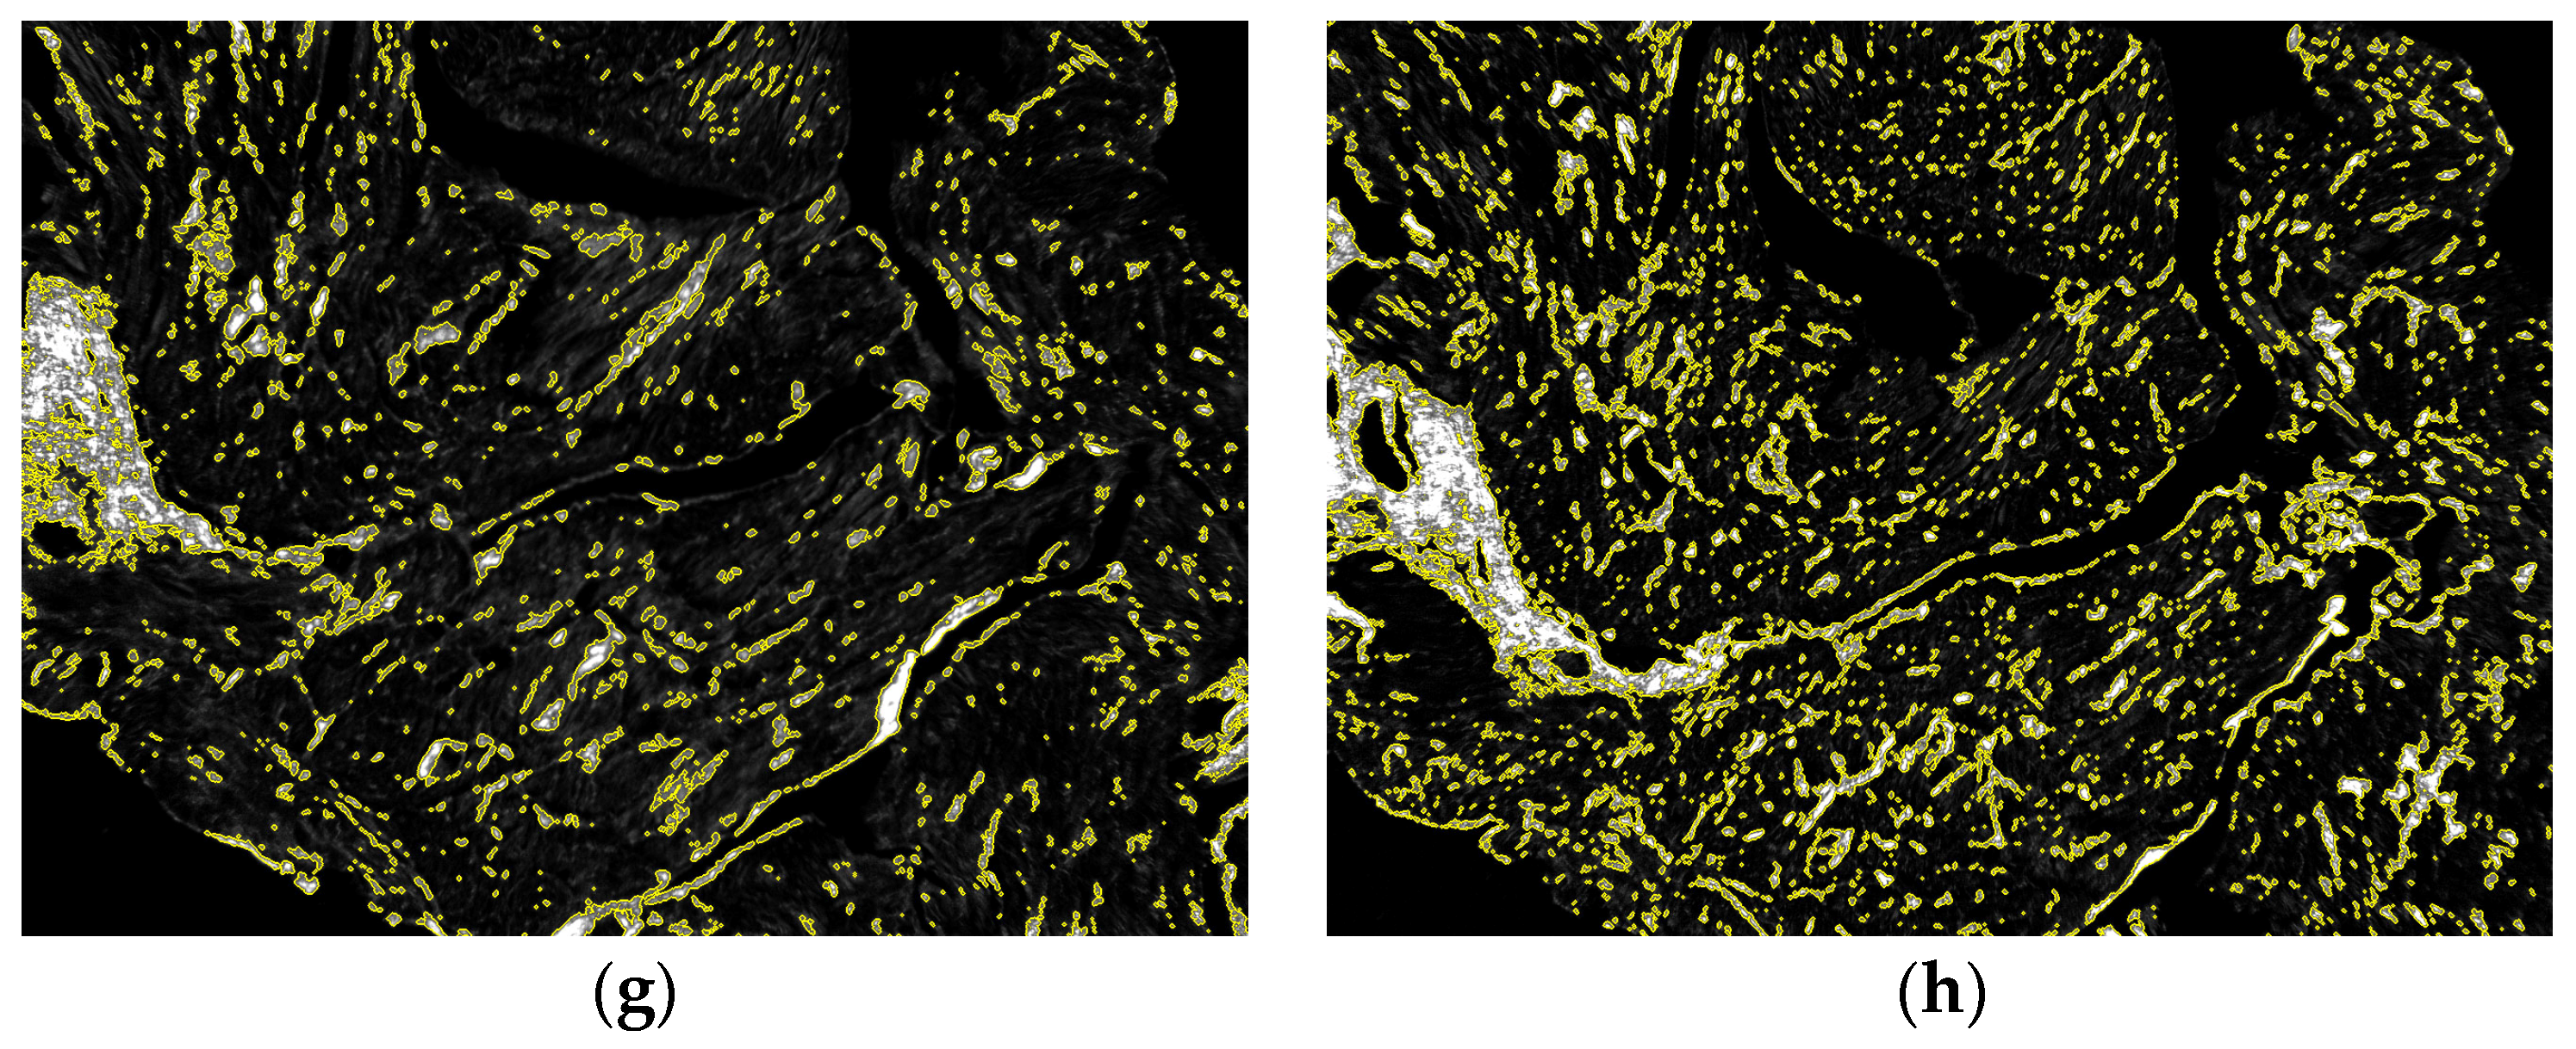

Figure 5 shows an example of the algorithm capability to compensate artifactual variability related to sample thickness. Two spatially close tissue sections, characterized by similar tissue composition but different thickness, were compared. At visual inspection, the tissue profile and the red stain distribution followed similar patterns, while the different section thickness affected the transmittance values (Figure 5a,b). In the original dark-field images, a difference in birefringent signal intensity was observed (Figure 5c,d), where the thicker section emitted a redder and more intense birefringent light. After thickness correction, the RGB birefringence images (Figure 5e,f) were more balanced in terms of intensity and chroma. The threshold = 0.152 on the greyscale collagen signal (Figure 5g,h) produced comparable fractions of collagen content (8.1% and 11.1%, respectively). It is to notice that a more fragmented collagen distribution was present in the thinner section, while in the thicker one the signal formed larger clusters, probably owing to the additive effects of a larger number of myocardial tissue layers.

Figure 5.

Correction for sample thickness variability. The robustness of the algorithm against sample thickness variability is examined comparing a slice of average optical thickness = 0.36 (left column) with a nearby slice of average optical thickness = 0.21 (right column): (a,b) The sample transmittances evidences the different tissue thickness between the two samples; (c,d) Original dark-field images (windowed 0–32,768); (e,f) RGB birefringence signal images (windowed 0–0.5); (g,h) Greyscale collagen signal images (windowed 0–0.5). The collagen mask for a threshold = 0.152 is contoured in yellow. The estimated collagen fractions were = 8.1% and 11.1%, respectively.